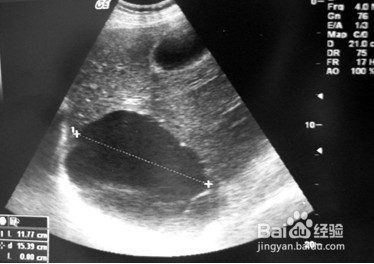

4、遇到囊肿如何处理:2.大的囊肿且出现疼痛、食后腹胀、恶心等情况的,可行B超下囊肿穿刺抽液术。B超下可以清晰地单靠囊肿位置、大小等,穿刺术非常安全。

1、肝脏囊肿属于常见疾病,对于大部分因体检发现的肝囊肿,都无明显症状,可不必去管,建议半年到一年定期B超复查,观察有无出现临床症状、囊肿大小;对于已经有压迫症状的,建议及时到医院就诊。